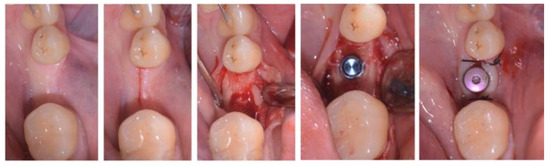

2.3. Treatment Procedure

- Case 1: